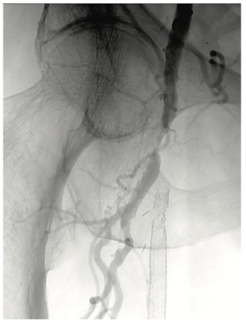

This case illustrates how robotic-assisted percutaneous coronary intervention (PCI) can be leveraged in a complex case involving multilevel arterial occlusive disease.